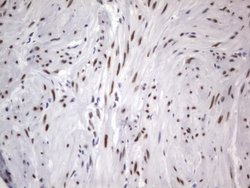

RBFOX1 Mouse anti-Human, Clone: OTI4F9, lyophilized, TrueMAB™

| Immunohistochemistry (Paraffin), Western Blot | |